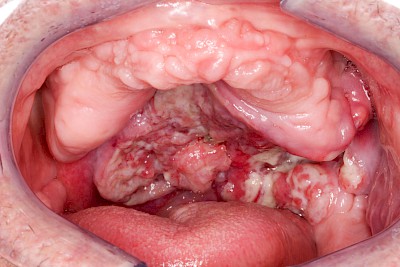

Einschmelzung & Geschwür

Das Risiko für Krebs der Mundhöhlen-Schleimhäute ist bei Menschen, die jahrelang übermäßig viel (Abusus) geraucht und erst recht lange übermäßig viel Alkohol getrunken haben, stark erhöht. Die Schleimhäute sehen dann aus wie "wildes Fleisch" – entweder mit blumenkohlartigen Auftreibungen oder aber es zeigen sich großflächige ungleichmäßig geformte Defekte und Einschmelzungen. Man spricht dann auch von einem Geschwür (Ulcus).

Selten können auch Fibrome oder Druckstellen bei Zahnprothesen, wenn diese nicht erkannt und behandelt werden, in "wildes Fleisch" übergehen und hin zu bösartigen Tumoren entarten.

Bei allen diesen Auffälligkeiten ist eine sofortige (zahn-)ärztliche Abklärung zu veranlassen.